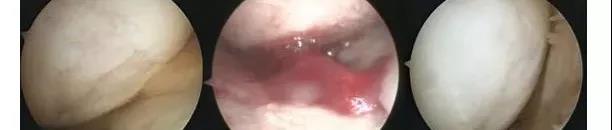

ÊõºóµÚ¶þ´Î¹Ø½Ú¾µ¼ì²é£¨Í¼a£©¡£ÔÚËùÓÐ4Ãû»¼ÕßÖУ¬ÒÆÖ²ÇøÓò¾ßÓб£´æÍêºÃµÄ͸Ã÷×´Èí¹Ç½á¹¹¡£4Àý»î¼ì±ê±¾µÄ×é֯ѧ¼ì²é½á¹û±íÃ÷£¬ÓëÁÚ½ü¹Ø½ÚÑ×Èí¹ÇÏà±È£¬ÐÞ¸´Ð§¹û¸üºÃ¡£×éÖ¯ÏÔʾ´æÔÚÈí¹Çϸ°ûÑùϸ°û£¬ÒÔ¼°Í¸Ã÷Èí¹ÇÑù½á¹¹ºÍ»ùÖÊ¡£ËùÓÐËĸö»î¼ì±ê±¾¾ùΪÎÞÒìλ¸Æ»¯ºÍѪ¹Ü»¯¡£²¢ÇÒûÓз¢ÏÖÑ×Ö¢¼£Ïó¡£

ÉÏͼaΪÖÎÁÆÇ°¹Ø½Ú¾µ¼ì²é½á¹û£¬¿ÉÒÔ¿´³öÈí¹Ç´æÔÚȱËð¡£Í¼bΪ֬·¾¼ä³äÖʸÉϸ°ûÁªºÏPRPÖÎÁÆ£¬Í¼cΪÖÎÁƺó½á¹û£¬Èí¹ÇµÃµ½ÁËÐÞ¸´¡£